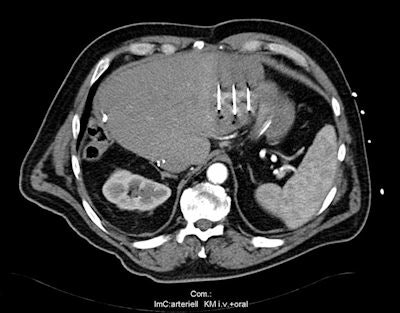

Above: MRI of an active liver metastasis near the gastric wall (parts of the liver had already been surgically removed two years previously). Below: Three IRE probes surround the tumor. Bottom: Signs of a tissue-sparing destruction of the liver metastasis in the CT review after the procedure.Images courtesy of Dr. Christian Stroszczynski, Regensburg University Hospital.

The interventional radiologist applies two to six probes to the main focus of the cancer. Imaging guidance, typically with CT, is used for navigating the probes, and once the scene of events is reached, a very strong electrical current -- of several thousand volts -- is applied to the tumor tissue, for a fraction of a second. The violent electrical pulse causes the membranes to open and the cells burst.